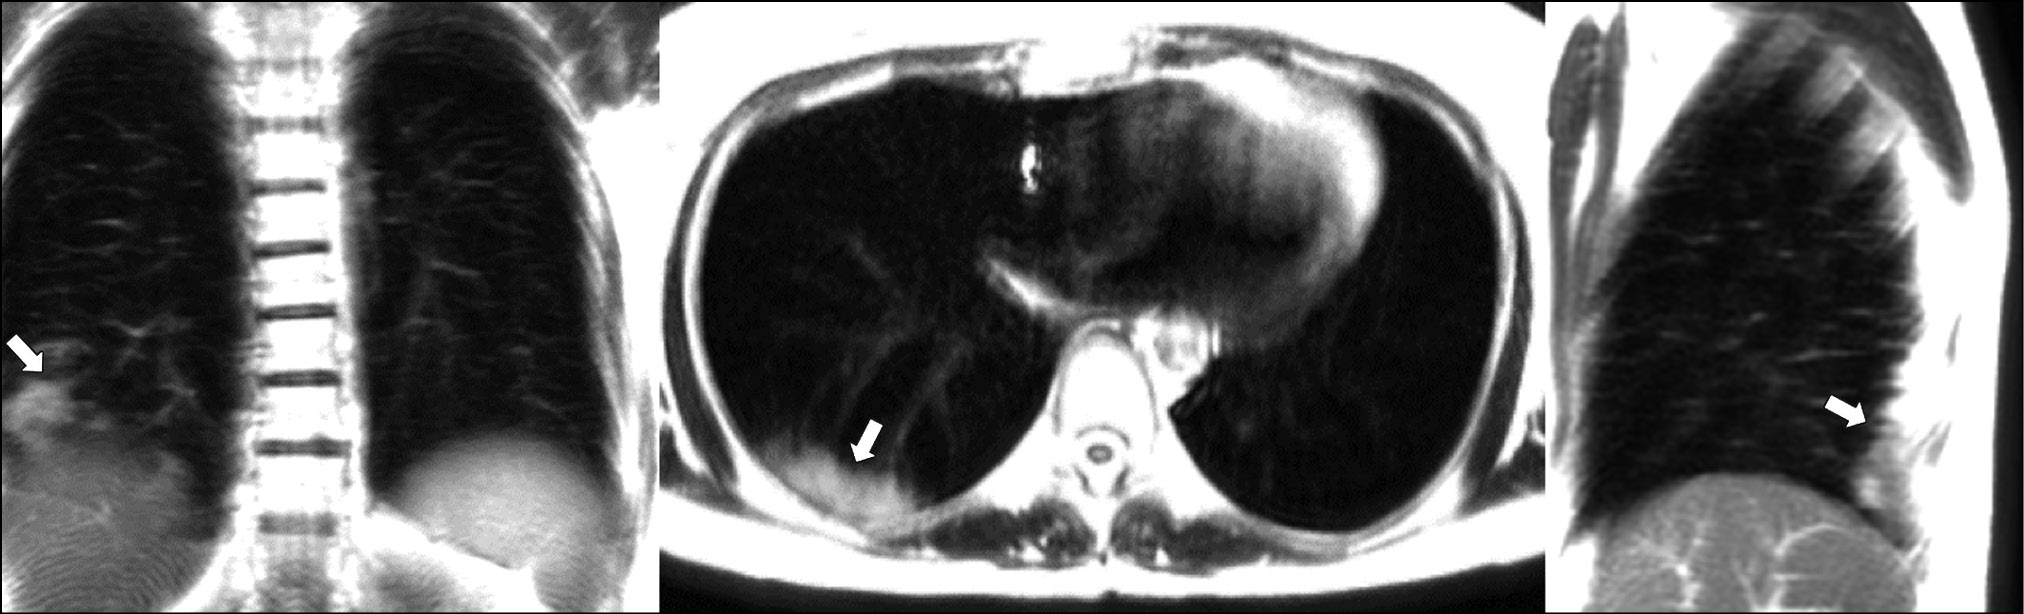

A patient (male, 49 years old) with a mild cough and subfebrile fever up to 37.5°С consulted a doctor on the second day after the onset of symptoms. Dynamic lung MRI showed the predominant “cloudy sky,” which was confirmed by different signal intensities and signal change area sizes depending on the respiratory cycle phase. During inhalation, a weak signal was detected in the lower lobe of the right lung (S6, S9, and S10) in the coronal, axial, and sagittal planes (Fig. 5). Increased signal intensities and area sizes were observed in the coronal and sagittal planes at the end of exhalation (Fig. 6) compared with the areas described. The “cloudy sky” was more prominent in the axial plane during exhalation, whereas the area of visible lung damage was wider.

Figure 5. Dynamic magnetic resonance imaging of the lungs during inhalation in the coronal, axial, and sagittal planes. Arrows point to areas of low-intensity signal with the “cloudy sky” pattern (S6, S9, and S10).

Figure 6. Dynamic magnetic resonance imaging of the lungs during exhalation in the coronal, axial, and sagittal planes. Arrows point to an increase in low-intensity signal areas with the “cloudy sky” pattern (S6, S9, and S10).